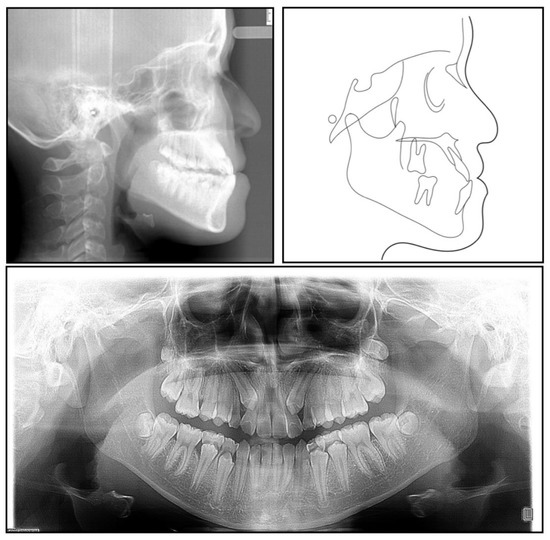

The panoramic radiograph showed that both the maxillary canines and all the third molars were impacted, and no significant periodontal support loss was found. The cephalometric analysis (Figure 3 and Table 1) showed a severe skeletal Class III relationship (ANB, −4.0°) with an insufficient developed maxilla (SNA, 77.2°). The maxillary incisors were relatively well-positioned, while the mandibular incisors were lingually inclined (U1-SN,104°; L1-MP, 86.5°) [8].

The final panoramic radiograph confirmed parallel roots with no apparent root resorption. Cephalometric analysis (Figure 9 and Table 1) indicated a normal anteroposterior (AP) relationship (ANB, from −4° to 1.3°) and decreased lower third (FMA: from 26.6° to21.5°; Na-Me: from 111.8 mm to 103.7 mm). Furthermore, the distance from the upper and lower lips to the E-line were significantly decreased, which helped improve the soft tissue profile.

Figure 3. A pretreatment lateral cephalometric radiograph and tracing and a panoramic radiograph.

Figure 9. Posttreatment lateral cephalometric radiograph and tracing and a panoramic radiograph.